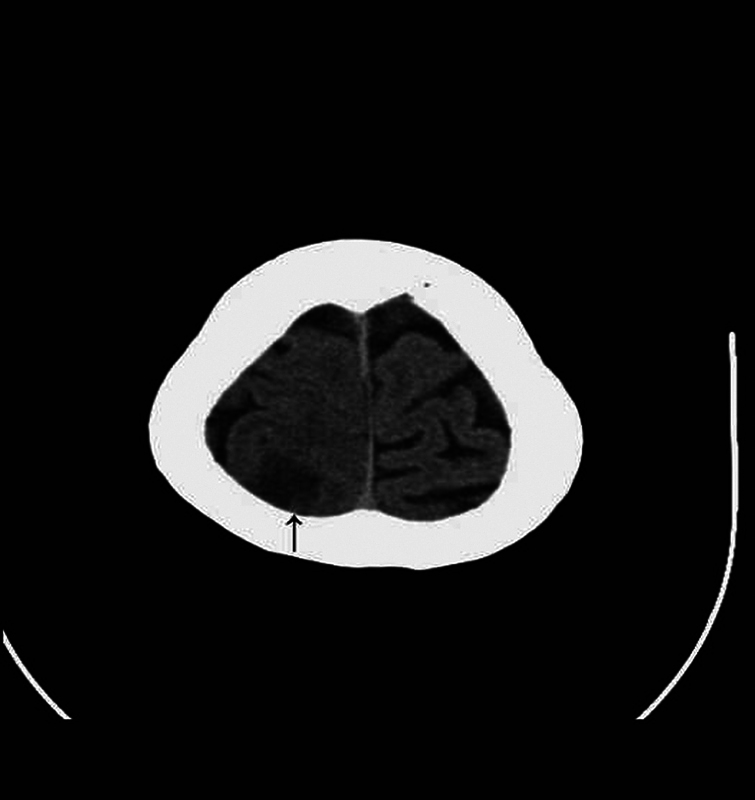

胶质瘤和脑膜瘤是两种常见的原发性脑肿瘤,但在同一患者中同时发生是罕见的。作者想报告一例共存的上顶叶弥漫性胶质瘤,idh野生型,组织学中枢神经系统WHO分级3级和左后窝移行性脑膜瘤,WHO分级1级;在一次手术中成功切除了两个肿瘤。一名68岁女性高血压患者向我们就诊,主诉为左下肢不自主震颤并伴有左上肢刺痛、头晕和颈部酸痛。她被发现在她的右顶叶区有一个病变,在她的左小脑区有一个肿瘤。在与患者详细讨论和全面的术前评估后,作者在一期手术中进行了右侧顶骨开颅和左侧乙状结肠后入路切除这两个肿瘤,证明这两个肿瘤具有两种不同的组织学特征。结论两个相距较远的肿瘤的治疗需要具体情况具体分析。在处理此类病例时,一个重要的方面是决定哪个肿瘤需要先手术,或者两个病变是否可以一次手术同时手术。

Introduction  Gliomas and meningiomas are two common primary brain tumors, but occurring simultaneously in the same patient is a rare entity. The authors would like to report a case of coexistence of a superior parietal lobule diffuse glioma, IDH-wild type, histologically CNS WHO grade 3 and a left posterior fossa transitional meningioma, WHO grade 1; both the tumors were successfully removed in one-stage operation. Case Presentation  A 68-year-old female having hypertension, who presented to us with the chief complaints of involuntary shaking of her left lower limb associated with her left upper limb tingle, dizziness, and neck soreness. She was found to have a lesion in her right parietal region and a tumor in her left cerebellar region. After detailed discussion with the patient and thorough preoperative evaluation, the authors performed a right parietal craniotomy and a left retrosigmoid approach in one-stage operation to remove both the tumors, which were proven to be of two distinct histological identities. Conclusion  The management for two tumors located far apart needs a case-by-case evaluation. An important aspect while dealing with such cases is to decide which tumor needs to be operated first or whether both lesions can be operated at the same time with one-stage operation.